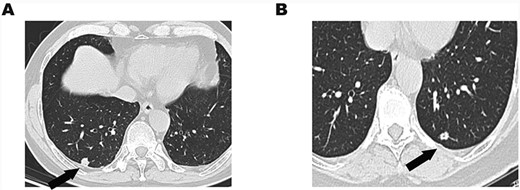

A 58-year-old man was admitted to our hospital due to abnormal chest shadow without any symptoms. Chest computed tomography (CT) revealed an 11-mm peripheral nodule in the right S10 segment (Fig. 1A). He received video-assisted thoracoscopic surgery (VATS), and wedge resection was carried out. The intraoperative frozen examination indicated papillary carcinoma and was unable to distinguish benignity from malignancy. Afterward, a right lower lobectomy was performed.

(A) Chest CT showed an 11-mm solitary nodule with central cavity in the right S10 segment. (B) An 8.5-mm solitary nodule with central cavity in the left S10 segment.

A 64-year-old woman was admitted to our hospital due to a gradually enlarged nodule in the left S10 segment. The nodule was about 5 mm when it was first found in 2007. It became 8.5 mm in 2019 (Fig. 1B). She insisted on receiving wedge resection instead of lobectomy even if the nodule was malignant. The intraoperative frozen examination indicated adenocarcinoma, and there is no further operation for her.